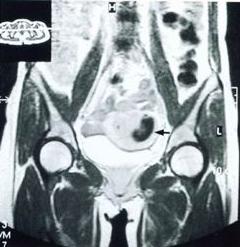

超聲檢查:B超是一種簡便、安全、無創傷的檢查方法。超聲診斷妊娠期闌尾炎的準確性與非孕期相同,並以早、中孕期效果好。